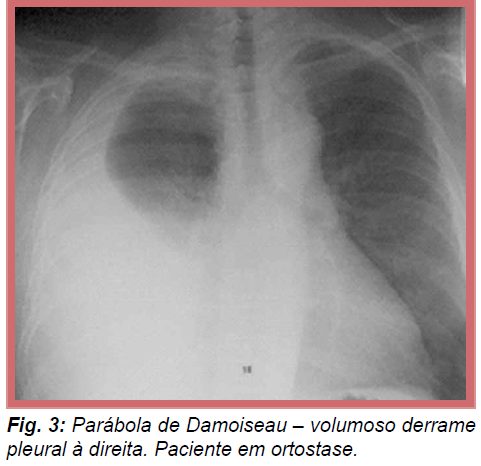

Como é o nome do achado radiográfico de um DP muito volumoso? Imagem. Explique.

Parábola de Damoiseau. O líquido está em toda a circunferência do tórax (circunferincial ao pulmão).